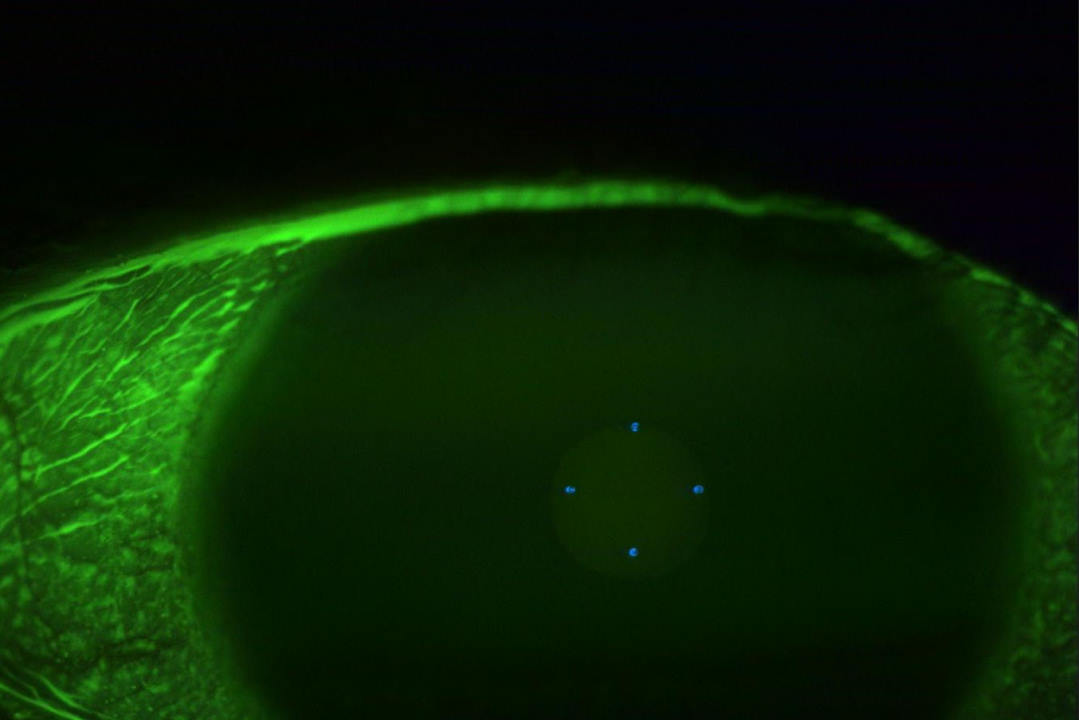

However, she returned after 10 days with a history of gritty sensation in the left eye and admitted to having rubbed it vigorously. Although the vision and IOP was maintained in the left eye, there was a retraction of the conjunctiva at the limbus, with broken sutures exposing the tube of the glaucoma implant. She was taken back to theatre where a very friable conjunctiva was sutured back. She continued with the same drops and at four-week follow-up presented with conjunctival erosion and an exposed tube of the glaucoma implant (Fig1). She maintained vision of 6/12 and IOP of 8mmHg in the left eye.

Fig 1. Conjunctival erosion with exposure of the tube of the Ahmed glaucoma valve implant